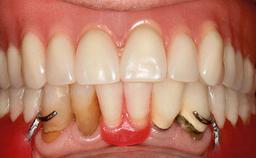

An 83-year-old man presented together with his caregiver at the dental department of the Medical University of Innsbruck, Austria with complaints of swelling in the right maxillary canine area and loss of retention of his 5-years-old mandibular denture. The patient had a significant medical history (20 years) of bipolar affective disorder with moderate depression (F 31.3) and dementia in Alzheimer’s disease (F 00.2). The patient had been in ambulant psychiatric therapy for his depressive illness for the past 20 years. He lived alone and had no children; his sister assisted with daily living. She reported that the patient exhibited compulsive hoarding behavior. In the previous two months, she had noted increasing disorientation and vertigo in the patient. She therefore accompanied him for a medical consultation at the Department of Psychiatry and Psychotherapy of the Medical University of Innsbruck. He was released home after a 6-week inpatient stay.

Periodontal Status History of periodontitis or genetic predisposition